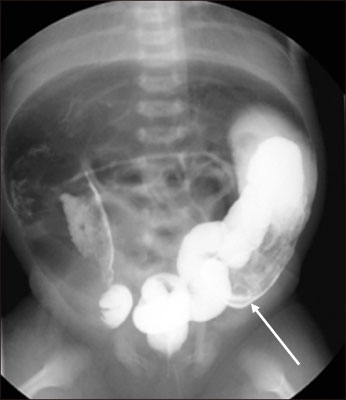

Table 1

Patients summary

ICV, ileocecal valve; M, male; F, female; SB, small bowel; TCA, total colonic aganglionosis; CMC, congenital megacolon.

Table 1 Patients summary